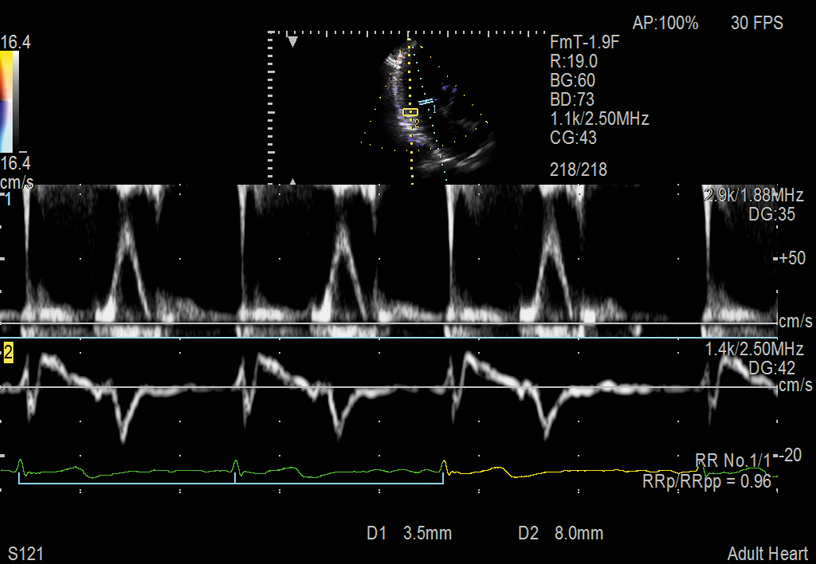

Dual Gate Doppler (DGD) can place two sample gates to detect waveforms of the same heartbeat, and the combination of PW and TDI is available. It is possible to perform diastolic performance evaluations such as E/e' measurement and TE-e' measurement stably by using DGD in combination with R-R Navigation, which automatically detects the appropriate heartbeat for measurement.